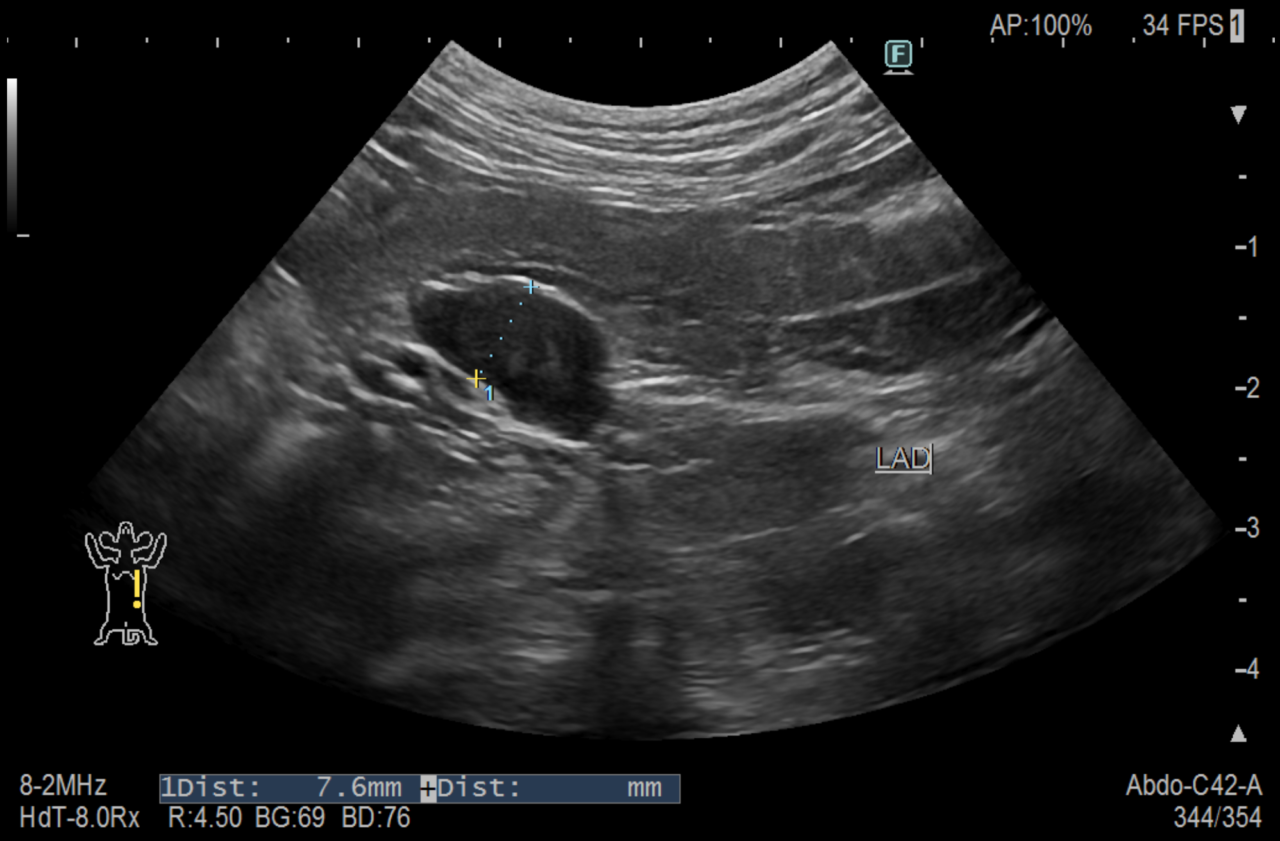

同時に行ったアルドステロン濃度検査では高値であり、画像検査では両側性の副腎腫大がありました。